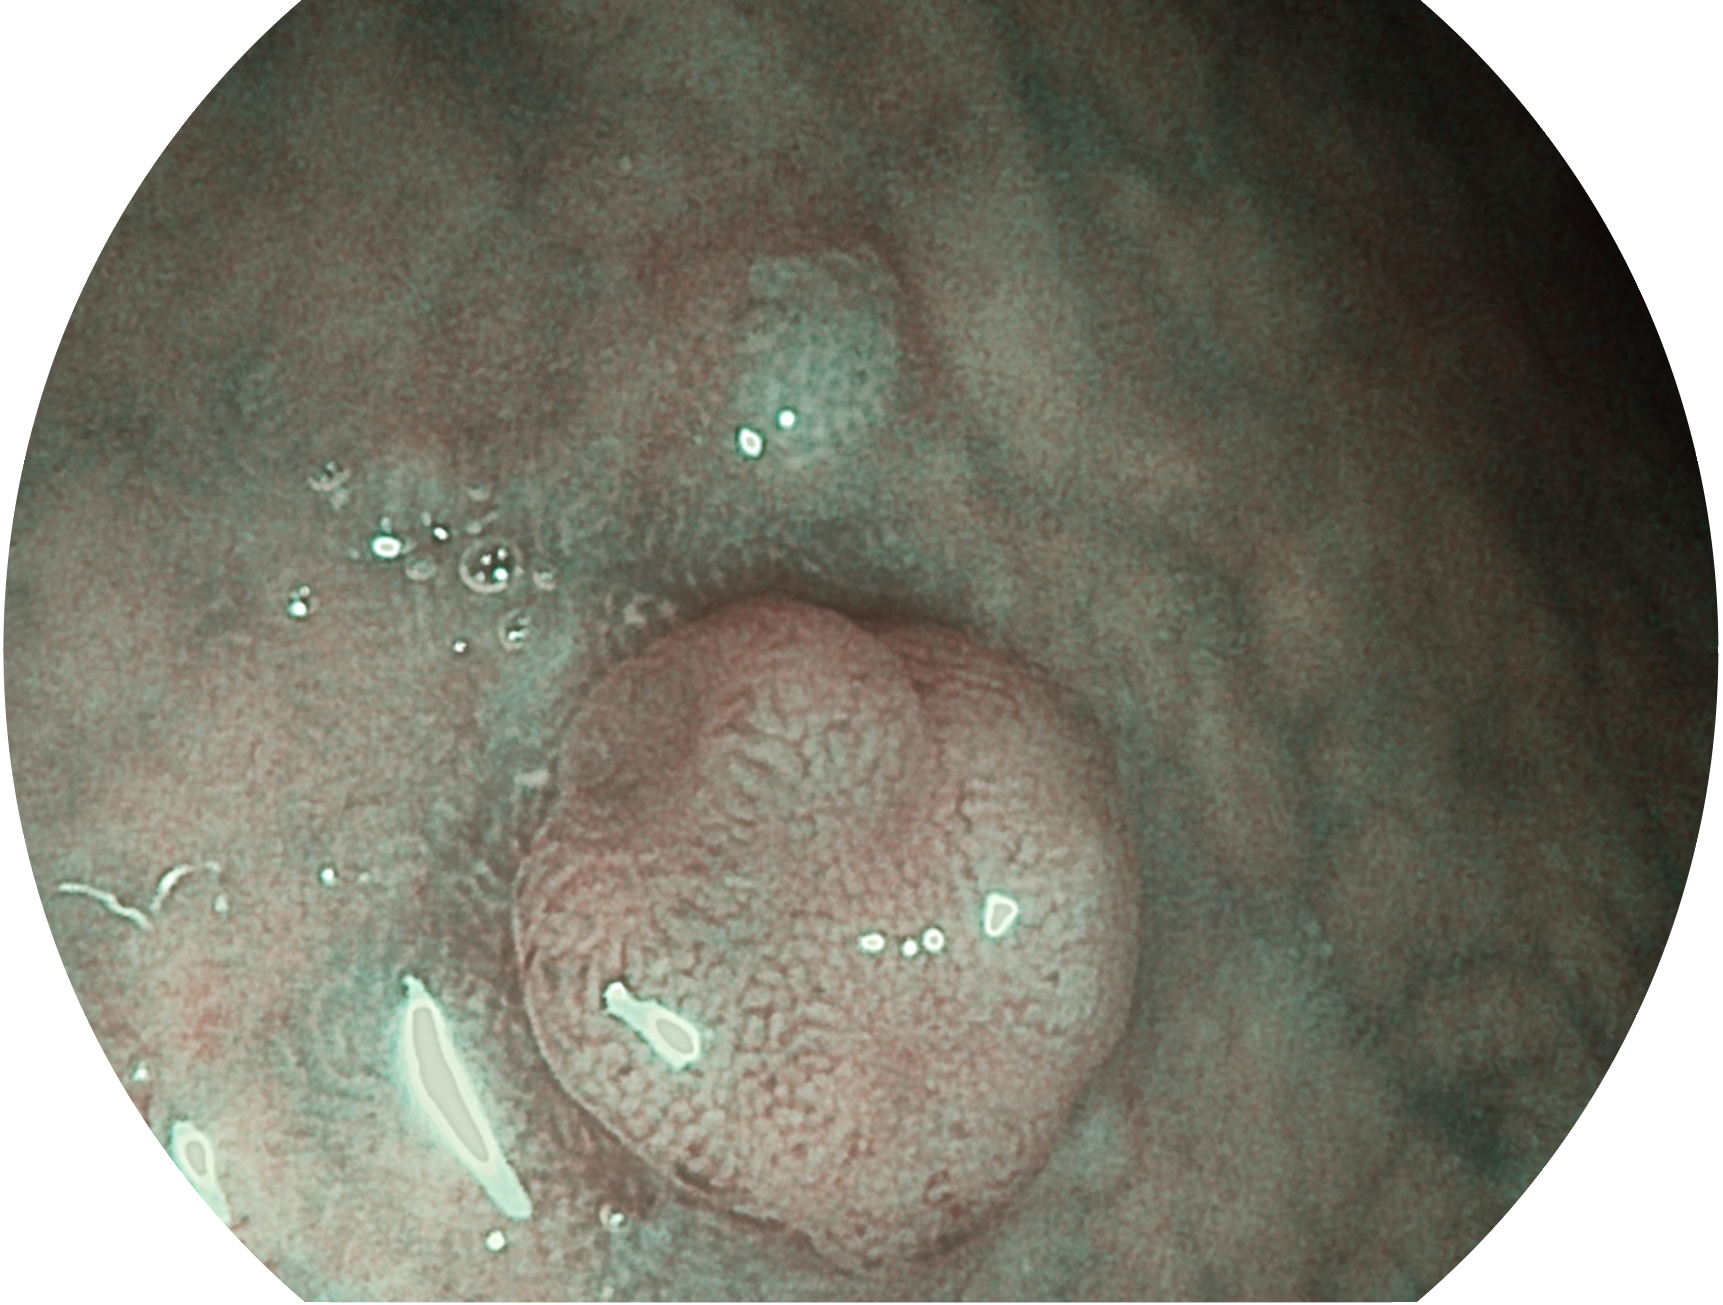

开立新开发的内镜染色技术,主要是基于多波长LED 光源的开发,VLS-55Q 四波长LED 光源是由四个不同颜色的LED光按照相应照明模式所规定的特定发光比例进行合束后形成,合束后形成的照明光的光谱由红光、绿光、蓝光及蓝紫光这四个不同的波段范围构成。具有更高光谱自由度,通过光谱比例的控制,实现了聚谱成像技术,英文全称为“Spectral Focused Imaging, SFI”,缩写为“SFI”和光电复合染色成像技术,英文全称为“Versatile Intelligent Staining Technology, VIST”,缩写为“VIST”。